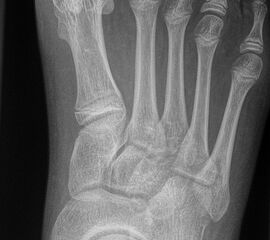

In der Regel bestehen aktive Wachstumsfugen bei Mädchen bis zum 12. und bei Jungen bis zum 14. Lebensjahr, mit Abweichungen von einem Jahr nach unten und nach oben. Präzise Informationen unter anderem darüber gibt das präoperative Röntgenbild (Abb. 2).

Abb. 2 a-c: offene Wachstumsfugen MT I Basis und Zehen (a), teilweise geöffnete Wachstumsfugen (b) und geschlossene Wachstumsfugen (c).

Zum Lesen der Bildbeschreibung und zur Vollansicht bitte die Bilder anklicken. Bilder: A. Helmers.